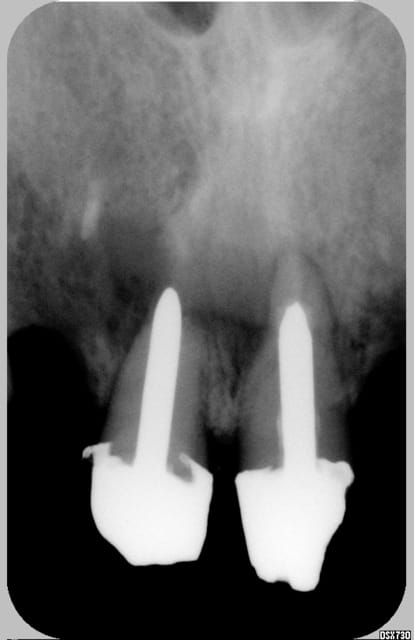

Plus d'info (radio ce soir...demain pour vous...)

Bonnes racines, pas de mobilité

Le sujet n'est pas la séquence, ni le plan de tx, mais savoir quelles dents IC ou bien tenons fibrés + résine...

Autre photo et une radio

Je suis 98% tenons fibrés + résines.

J'ai débuté en 1994, avec les tenons carbones, puis les quartz. C'est pas une études scientifique, ni pour la vente d'un produit, c'est seulement ma p'tite expérience.

Dans les molaires, parfois pas de tenon, selon le cas.

Pour la question d'avec ou sans IC, il serait important de connaître les paramètres radiculaires (longueur principalement). Avec des longues racines de mamouth, je ne mettrai pas d'Ic.

Avec de bonnes racines, moi je mets des tenons fibrés partout.